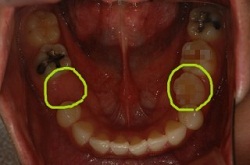

연두색으로 동그라미 친 위 왼쪽 하나, 아래 양쪽 하나씩

아까 보앗던 입속사진을 다시 보면

왼쪽 동그라미가 유치고 오른쪽 동그라미는 영구치에요

크기 차이가 보이시나요??

작은 영구치가 나야할 자리를 커다란 유치가 차지하고잇으니 치열이 앞으로 밀려나오게 된거래요